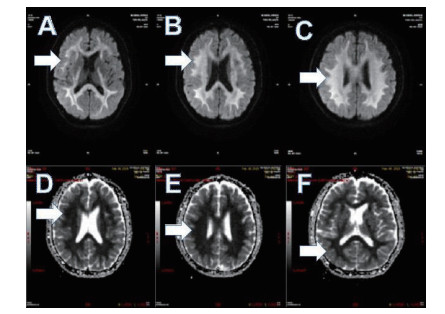

磁共振提示胼胝体局灶病变多为轻症患者(图 3);磁共振提示胼胝体双侧放射冠部散在病变多为中型患者(图 4);磁共振提示胼胝体双侧放射冠区弥漫性病变多为重症患者(图 5,6)。

| 图 3 ABCD为同例患者,病变为胼胝体局灶病变(箭头所示);EFGH为同例患者,病变为胼胝体右侧放射冠区局灶病变(箭头所示) |

| 图 4 此图为中型患者,可见胼胝体双侧放射冠部散在病变 |

| 图 5 重型患者,可见胼胝体双侧放射冠区弥漫性病变 |

| 图 6 重型患者,可见胼胝体双侧放射冠区弥漫性病变 |